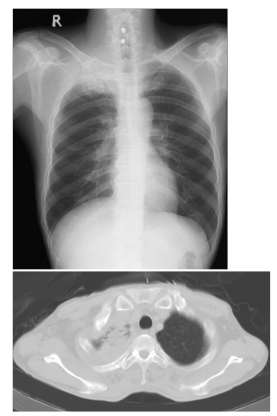

1.51歲男性病患,因為近半年來右上背酸痛和右上肢麻痹和無力到院就醫。他因這些病症在他 院接受止痛藥物治療和手術治療頸椎椎間盤突出開刀,但症狀未見改善。到院前三個月,他開始出現右眼皮下垂和視力模糊。他過去抽菸,一天一包達三十年之久。到院胸部X光和電腦斷層檢查如圖。多次痰液微生物顯微鏡檢和培養均為陰性。以下何者是最有可能的診斷?

(A)pancoast tumor(B)過敏性肺部氣管麴菌感染(allergic bronchopulmonary aspergillosis)(C)肺膿瘍(lung abscess)(D)肺部動脈靜脈畸形(arterio-venous malformation of the lung)